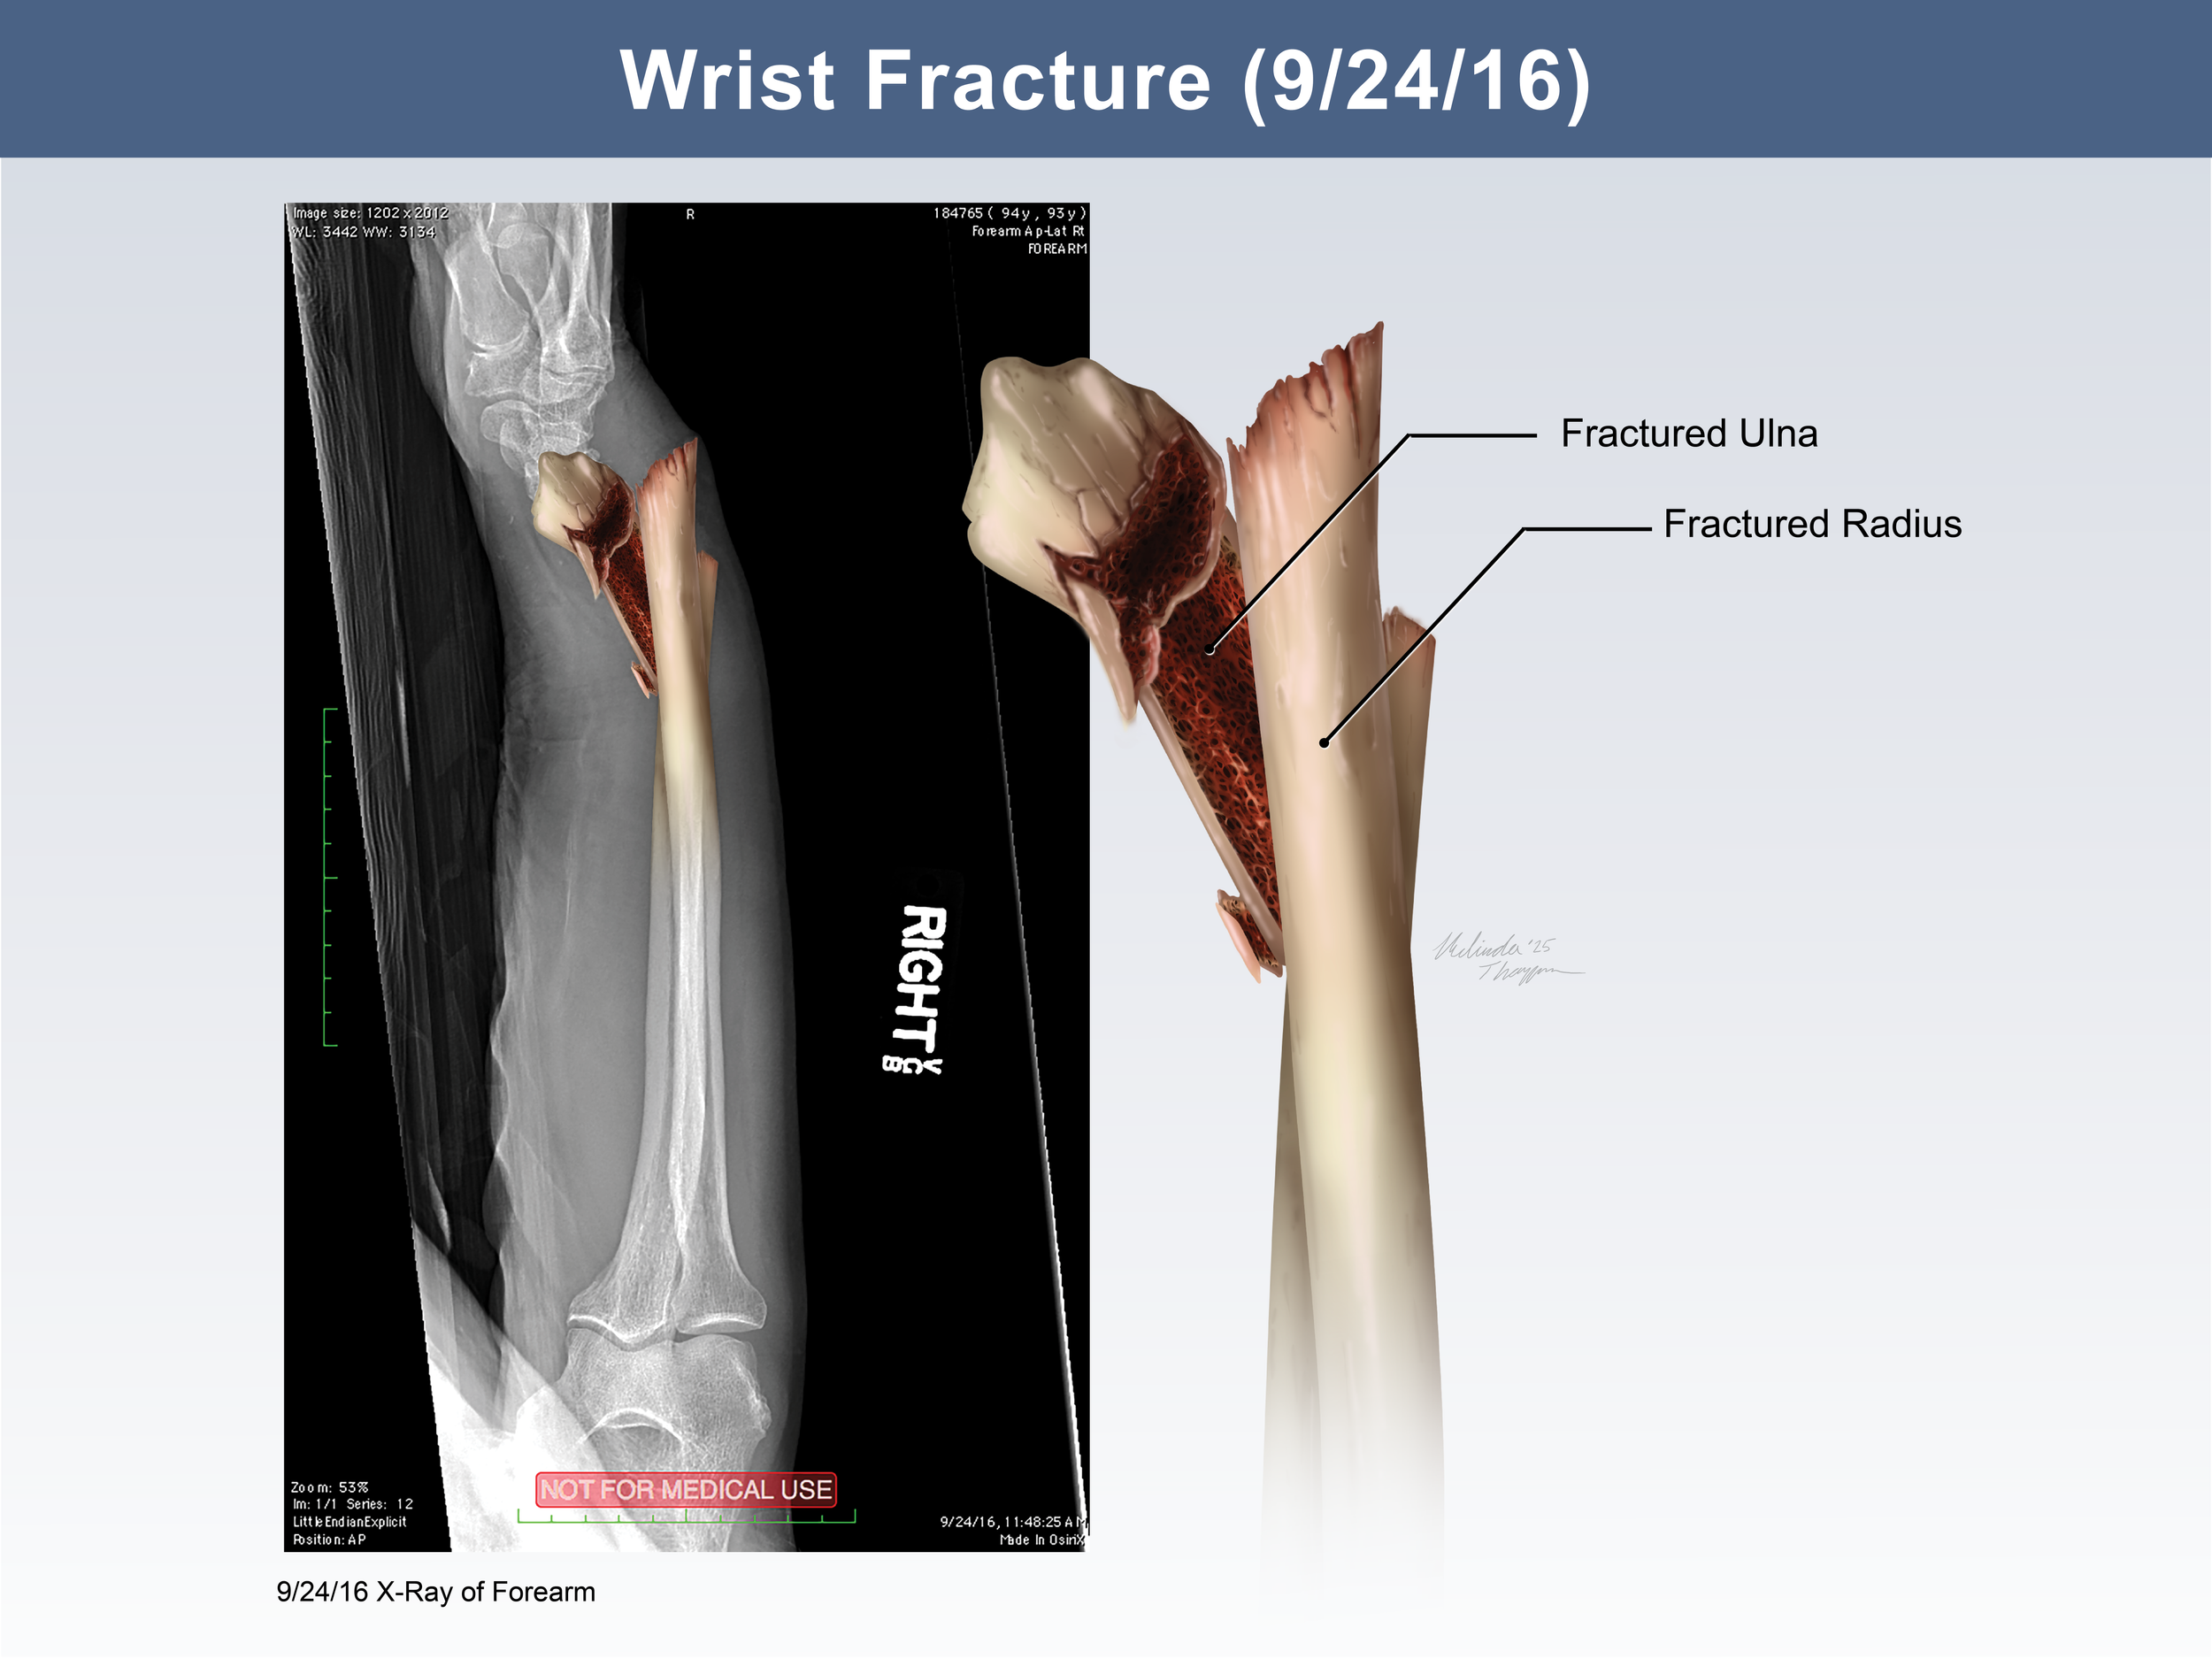

Medical Legal Illustration

Medical Illustration is important in the courtroom for many reasons including communicating scientific information for a lay audience, highlighting injury or anatomical differences, or simply representing potentially disturbing images in a more digestible way. Legal illustrations must be accurate, but still serve to help tell the defendant or plaintiff’s story.

Additional Medical Legal Illustrations

Wrist Fracture: X-Ray Illustration